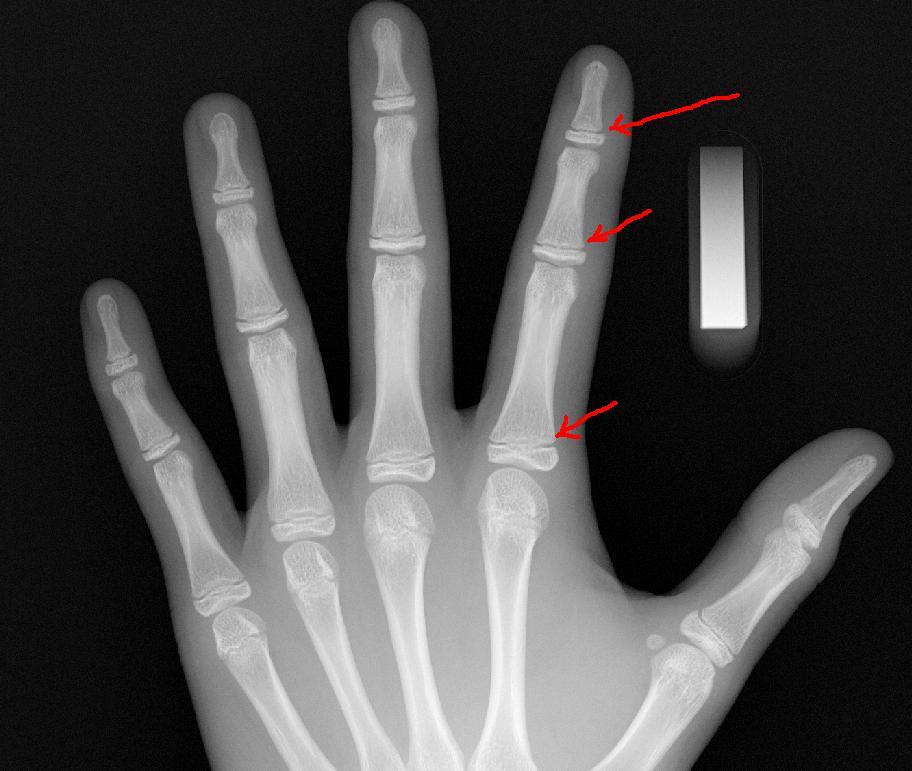

성장판 검사를 통해 성장판이 어느 정도 열려있고, 또 앞으로 얼마의 성장을 보일 것인가에 대한 예측도 중요하겠지만, 성장판 검사의 주 목적은 그 보다는 실제 아이의 나이와 뼈나이, 골연령과의 차이를 보기 위함이 더 큰 것입니다.

또한, 당장의 검사결과수치가 아니라 그 변화과정을 볼 수 있어야하기에 1년에 한 번, 또는 반년에 한 번, 경우에 따라서는 3달마다 검사를 반복하면서 골연령 진행속도를 보면서 성조숙증 여부를 체크할 수 있는 중요한 검사의 하나입니다.